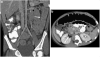

Results: The most common presenting symptoms were abdominal pain, bloody diarrhea and rectal bleeding. EC was characterized as a dense and predominantly eosinophilic inflammatory infiltrate in the lamina propria or epithelium without granulomas. CT scans were abnormal in six children (86%), demonstrating colonic wall thickening, predominantly cecal, in five (71%), mild to moderate terminal ileal thickening in two (29%), and pneumatosis in one (14%). Right colonic involvement was greater than terminal ileal involvement.

Conclusion: CT imaging findings in children with EC include right colonic wall thickening of variable extent downstream and absent or mild involvement of the terminal ileum. EC should be considered in the differential diagnosis in children presenting with abdominal pain and bloody diarrhea.